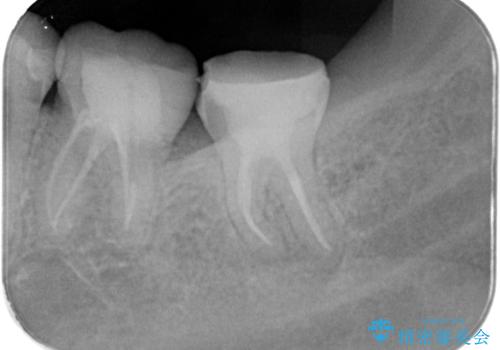

レントゲンや口腔内所見にて以下のような説明ののち、患者様が保存を希望されたため、当院では根管治療~オールセラミッククラウンにて修復処置を行いました。痛みも消えて、経過良好です。

根尖部に透過像を認め、①何もしないと今後の経過として痛みが増悪することや、腫脹を伴うことがある。

病気の原因は細菌であるため、細菌数を減らすための処置として一般的に②根管治療という選択肢がある。再根管治療の場合は病気が治るのは7割ぐらいであり、それでも治らない場合は意図的再植術を行い9割近くまで成功率を高めることができる。ただし、今回のケースでは根尖が湾曲しているため意図的再植時の破折リスクが高いため適応は難しい。また、根尖の病変が治ったとしても、歯周病、カリエス、脱離や破折リスクがあり治療後抜歯になる可能性もある。治らない可能性や治療したとしても抜歯になる可能性があることを考慮し、③抜歯の選択肢をとる場合もある。

今回の患者さんも同様に考えていたため、保存治療となったが、治療選択は患者さんの状況と術者の説明で変わるものである。